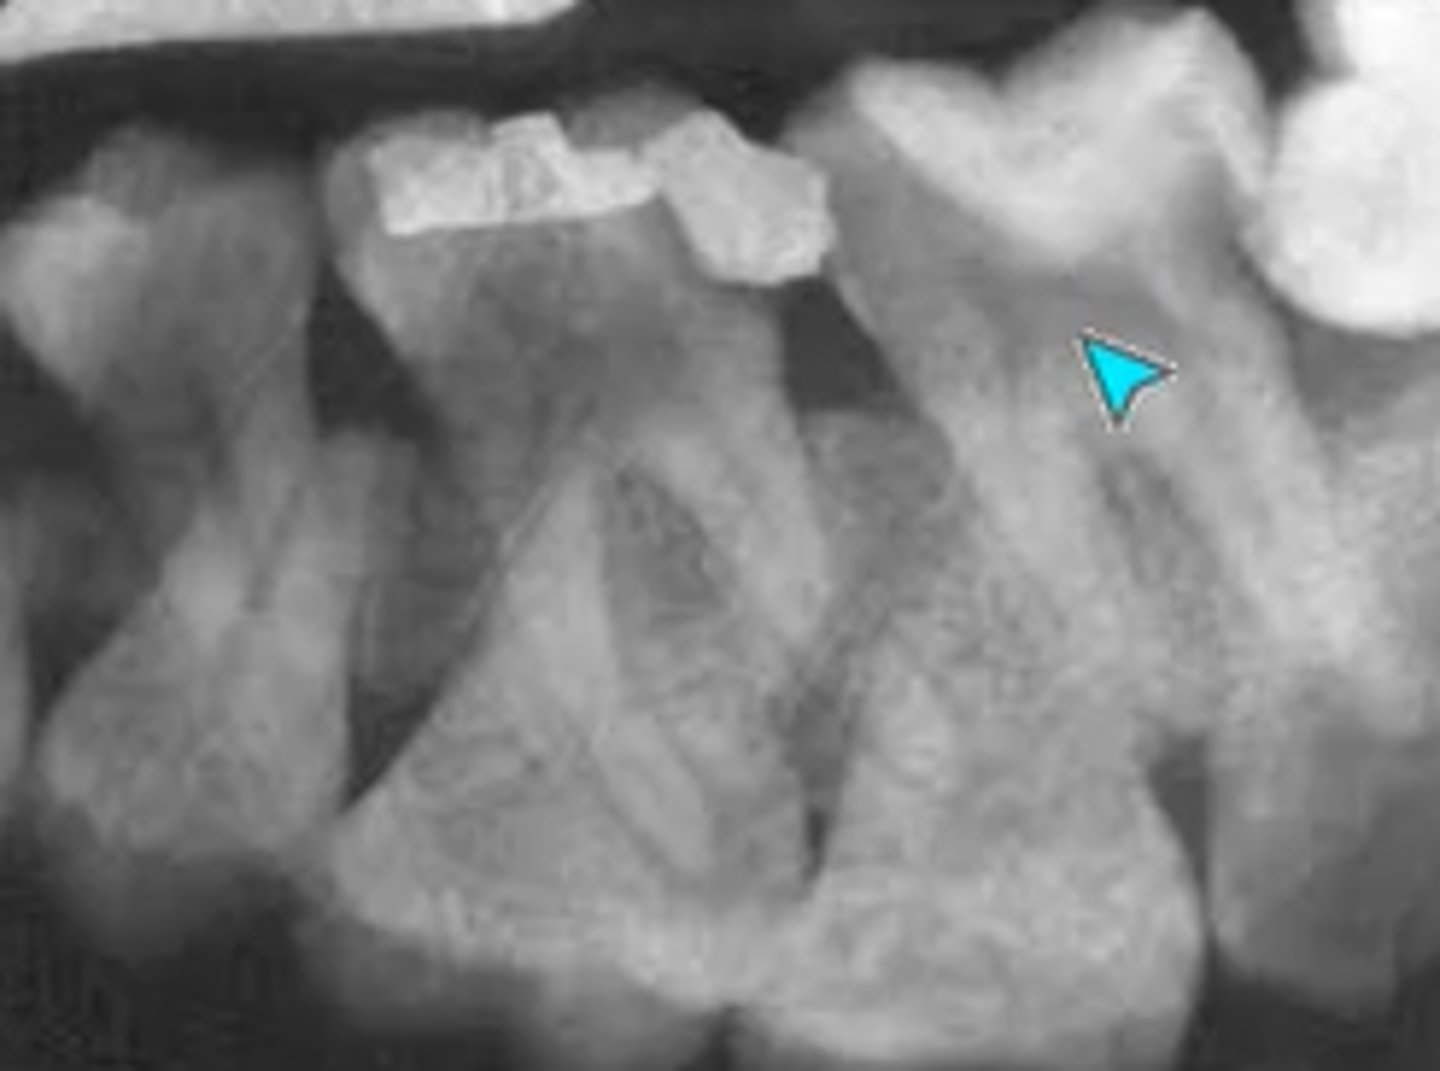

What error occurred here?

- Fixer time or temperature too high

- Radiograph light